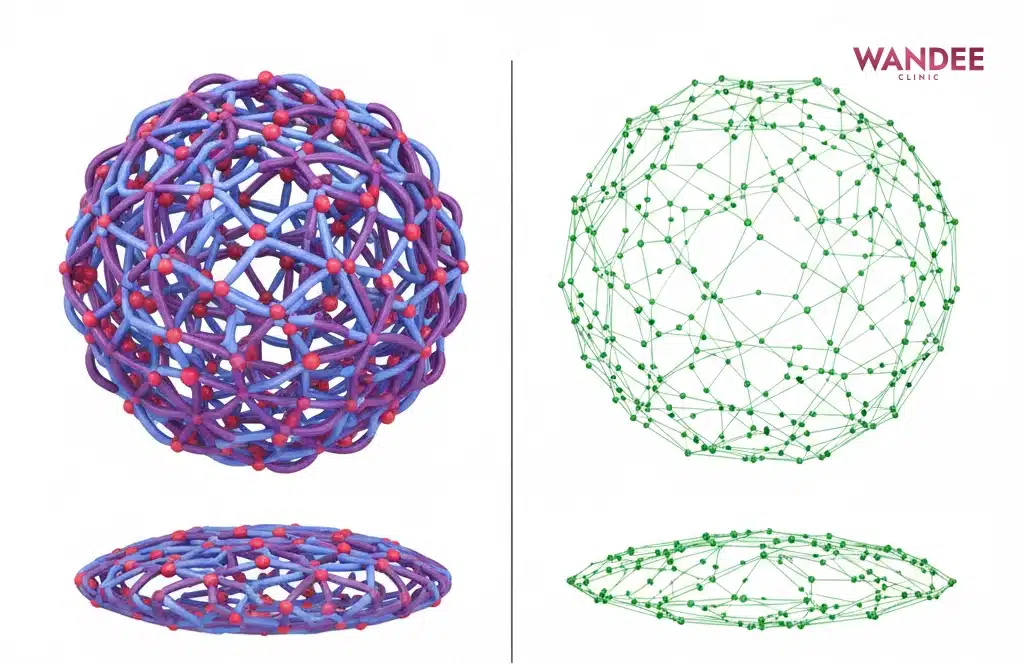

ภาพ: โครงข่ายที่แน่นมักคงรูปและพยุงได้มากกว่า ส่วนโครงข่ายที่หลวมมักนิ่มและเสียรูปง่ายกว่า จึงต้องเลือกให้เหมาะกับตำแหน่ง

เนื้อฟิลเลอร์มีผลกับความรู้สึกฟูและความนิ่งหลังฉีด เพราะเจลแต่ละรุ่นถูกออกแบบให้ต่างกัน บางรุ่นเน้นความเนียน บางรุ่นเน้นแรงพยุง เมื่อเลือกเนื้อไม่เหมาะกับตำแหน่ง อาจทำให้ดูแน่นหรือฟูเกินได้

คำว่า Cross link สื่อถึงโครงข่ายของเจล ส่วนค่า G Prime สื่อถึงความพยุงและความแน่นของเจล ในเคสที่ต้องพยุงฐานอาจใช้เนื้อที่พยุงได้ดี ส่วนผิวบางมักเน้นความเนียนและการกลืนกับผิว

- Cross link โครงข่ายของเจล ยิ่งแน่นมักยิ่งนิ่งและคงรูป แต่ต้องเลือกให้เหมาะตำแหน่ง

- Crosslinked HA gel ฟิลเลอร์ HA ที่ทำโครงข่ายเพื่อให้อยู่ทรงและสลายช้าลงตามรุ่น

- Rheology พฤติกรรมของเจล เช่น ความนิ่ม ความแน่น การไหลและการคืนรูป มีผลต่อความเนียนและความฟู

- G Prime (G’) ค่าความพยุงของเจล ค่าสูงมักเหมาะกับงานพยุง ค่าต่ำมักเด่นเรื่องความเนียน

- Structural support แนวคิดพยุงฐานชั้นลึก เพื่อให้เงาและร่องดูตื้นลงโดยไม่ต้องเติมตื้นเยอะ